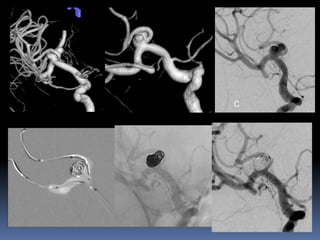

Fusiform, dissecting aneurysm

38 yr old male patient, 2-day old SAH

Known hypertensive

Clinically grade II

Small Blister/dissecting Friable, continued growth, re-rupture